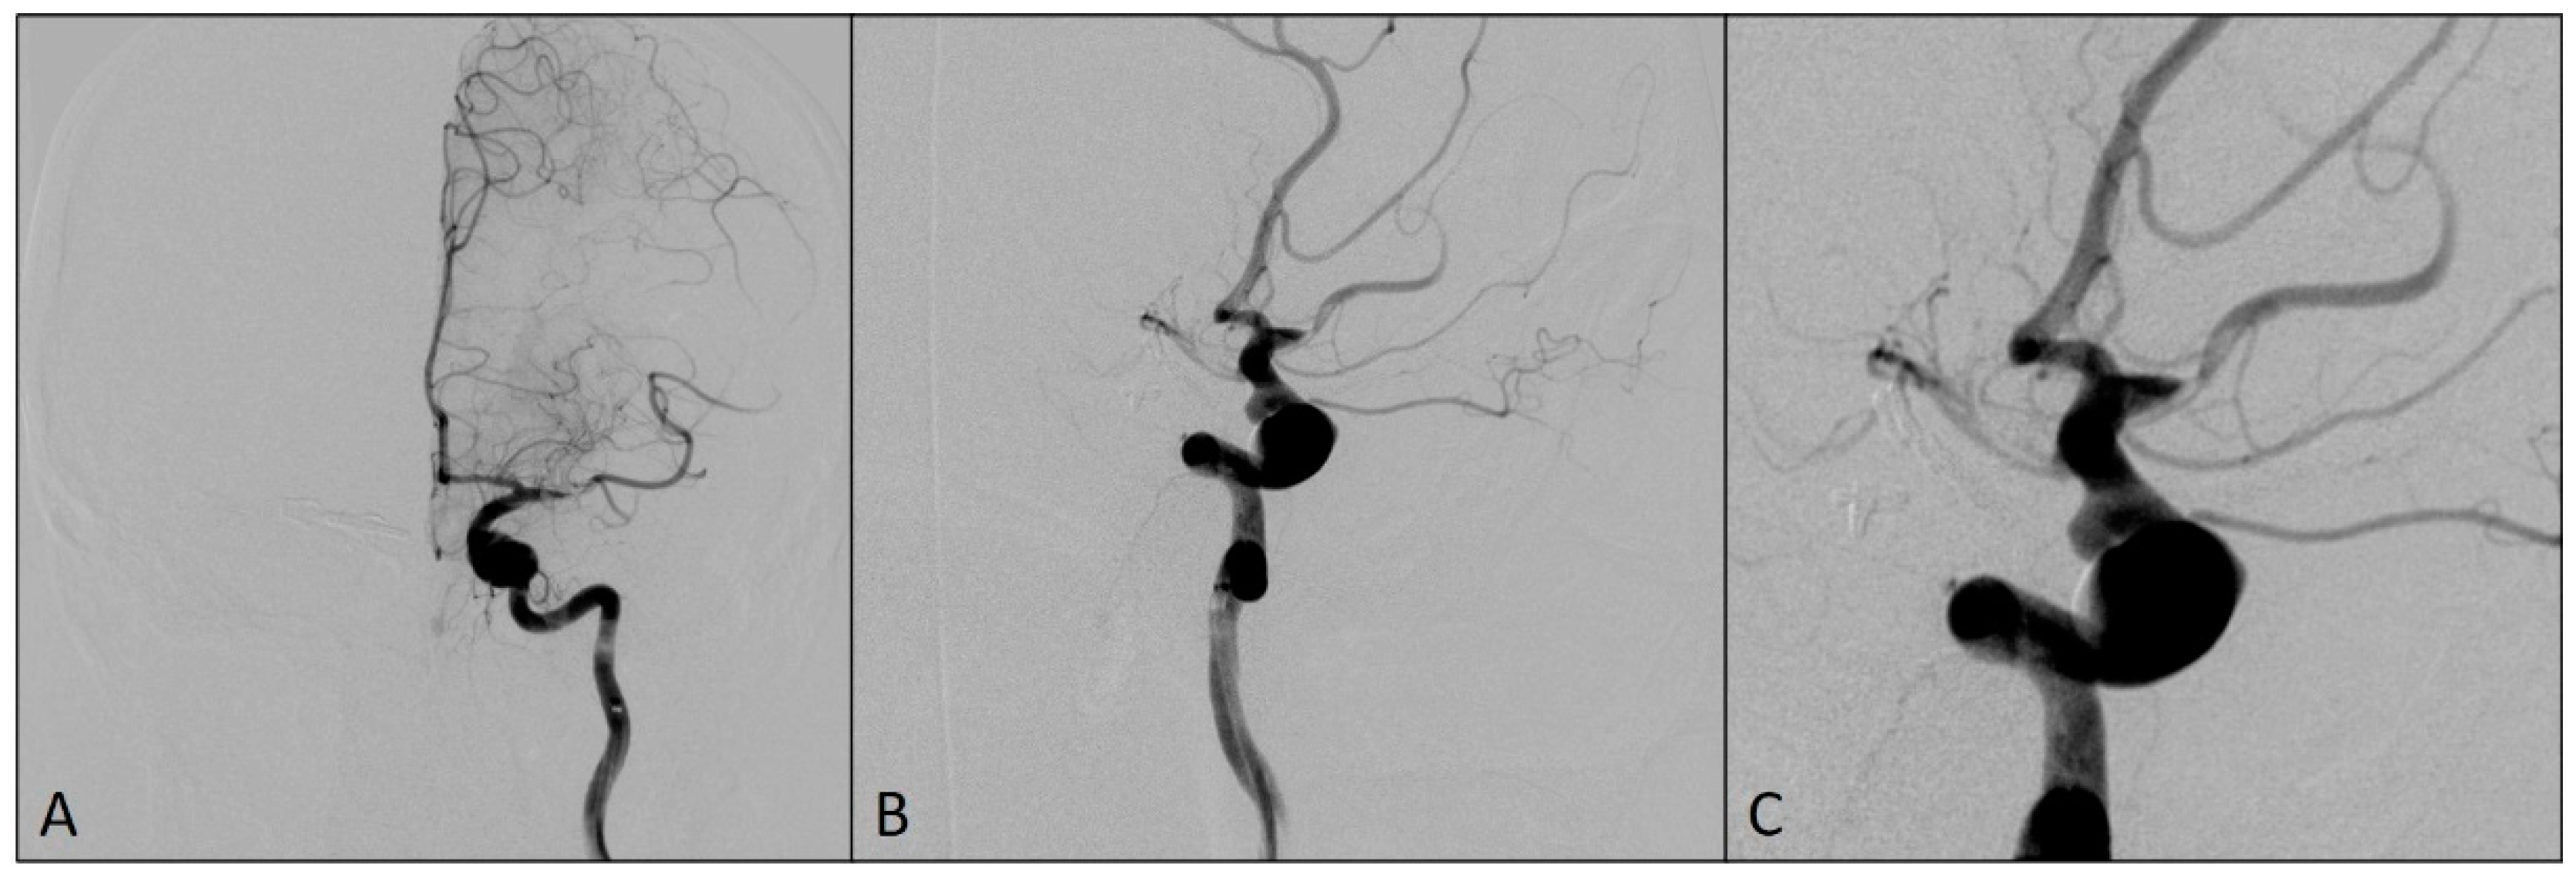

2. Case Report